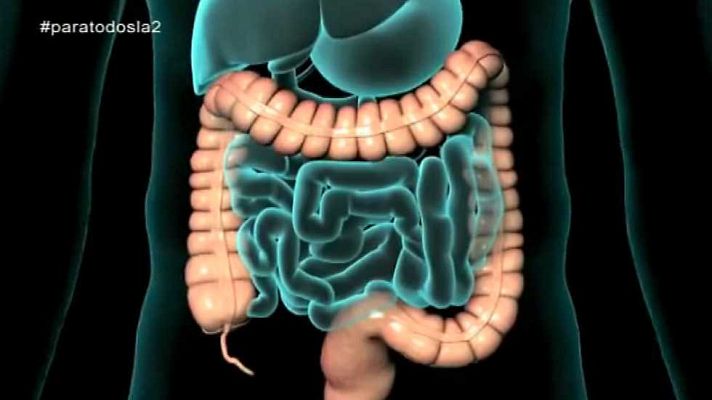

El cáncer de colon va en aumento. Es el segundo en mujeres y el tercero en hombres. La importancia de prevenir y detectarlo precozmente. Reportaje...

El cáncer de colon va en aumento. Es el segundo en mujeres y el tercero en hombres. La importancia de prevenir y detectarlo precozmente. Reportaje y coloquio con Isabel Portillo, coordinadora del programa de cáncer colorrectal en Euskadi y Fernando Carballo, médico del aparato digestivo del hospital Virgen de la Arrixaca de Murcia.